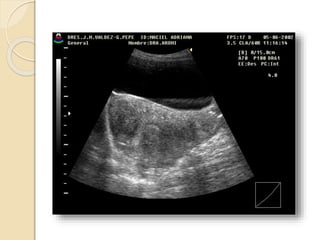

FIBROMA O LEIOMIOMA UTERINO

Patología común del útero que ocurre aproximadamente

en el 40% de las mujeres mayores de 35 años.

Los fibromas habitualmente son múltiples y más

comúnmente asintomáticos.

Se clasifican en:

• Submucosos: son los menos frecuentes pero es mas

probable que produzcan síntomas.

• Intramurales: Es el tipo mas común.

• Subserosos: Con frecuencia son pediculados y

pueden simular masas anexiales.